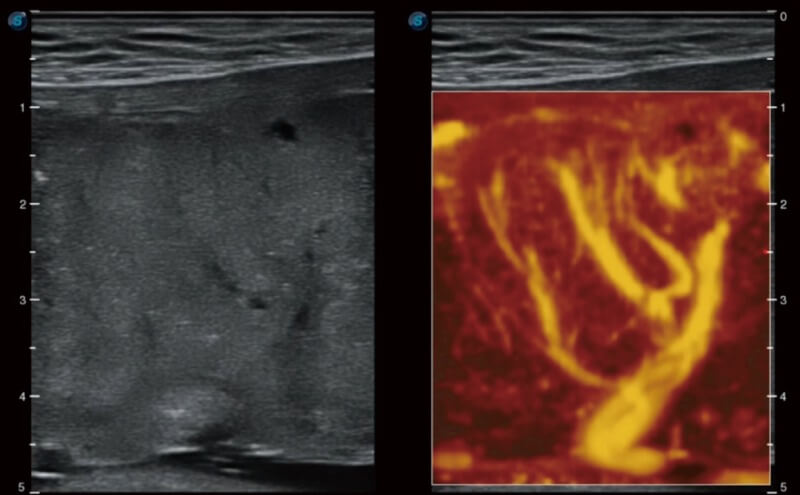

Ultraschall wird immer vielseitiger und übernimmt immer mehr klinische Aufgaben. Als Vorreiter, der Ärzten dabei hilft, mehr zu erreichen, ist ELITE mit einer umfassenden Palette fortschrittlicher Funktionen für die Allgemeine Bildgebung, Gynäkologie/Geburtshilfe, Kardiologie und mehr integriert.

Ultraschall wird immer vielseitiger und übernimmt immer mehr klinische Aufgaben. Als Vorreiter hilft ELITE den Ärzten dabei, mehr zu erreichen, indem es mit einer umfassenden Palette fortschrittlicher Funktionen ausgestattet ist, die die allgemeine Bildgebung, die Geburtshilfe/Gynäkologie, die Kardiologie und vieles mehr abdecken.